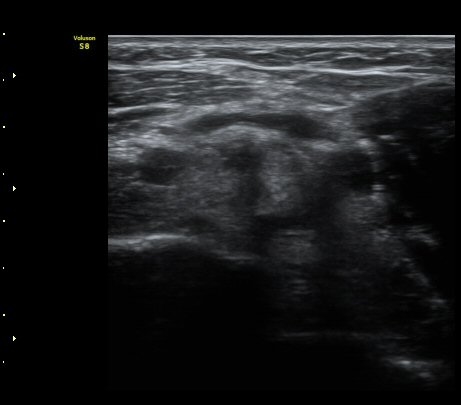

ÆÈ²ÞÄ¡ µÚÂÊ °üÀý¸éÀ¸·ÎºÎÅÍ 2.5cm ¾Æ·¡¿¡¼­ ¿ä°ñ°ü°ú ô°ñ °æ°èºÎ¸¦ Ⱦ´Ü¸éÀ¸·Î

°Ë»çÇÏ´Ï ¿ä°ñµÎ¿¡ ºÎÂøµÈ À̵ιڱ٠ÈûÁÙÀÌ °üÂûµÈ´Ù(±×¸² 9). Á¾´Ü¸é°Ë»ç¿¡¼­µµ

À̵ιڱ٠ÈûÁÙ°ú ¿ä°ñµÎ°¡ ¶Ñ·ÈÈ÷ °üÂûµÈ´Ù(±×¸² 10).